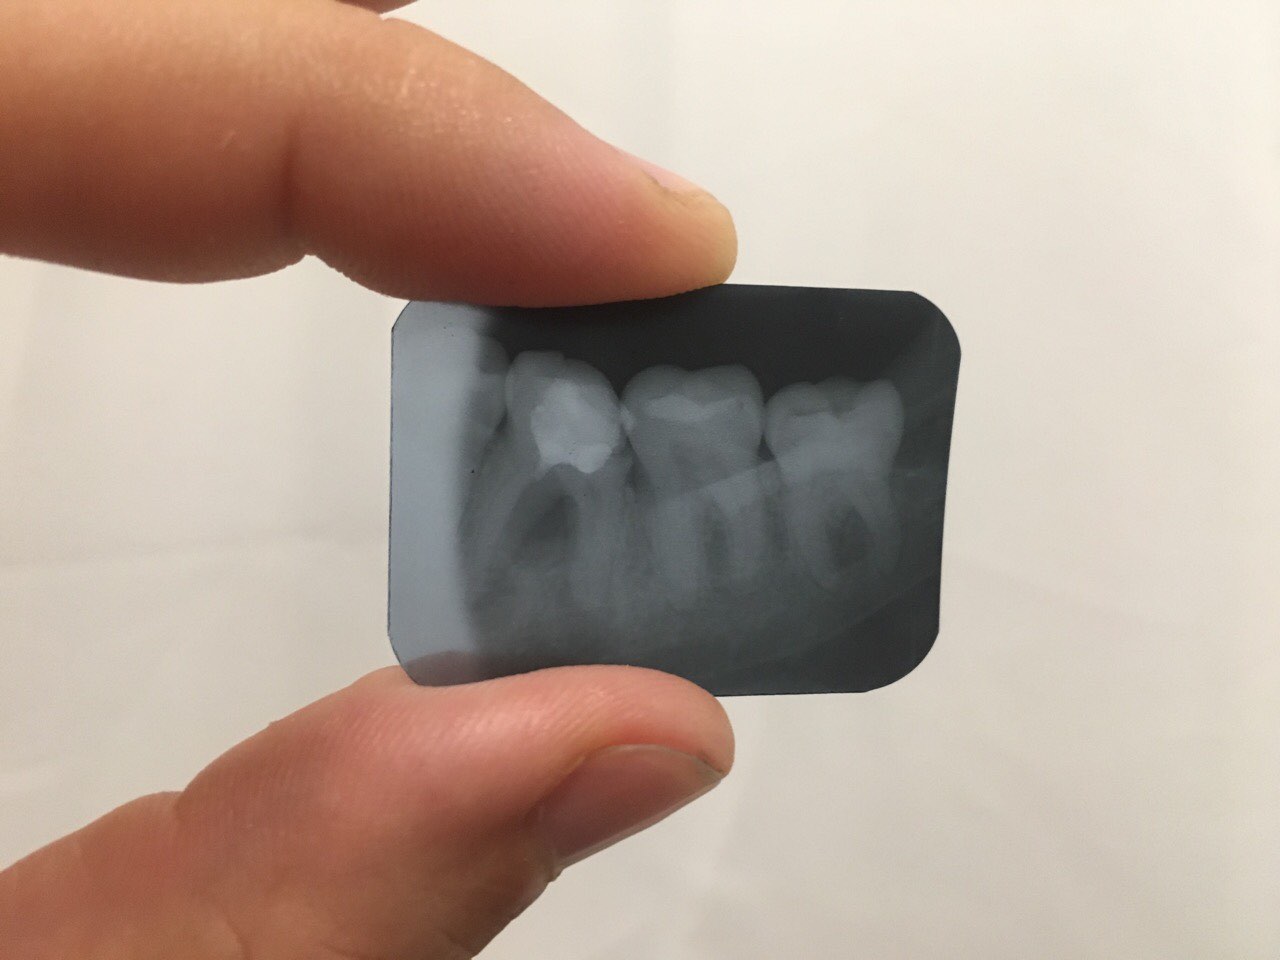

Вот зубик, который удалили сегодня(6ка внизу). 2 врача сказали удалять, а я сейчас смотрю на снимок и думаю, может надо было в Киев поехать, может там бы его спасли. Грустно без зуба и пустовато как-то Подскажите, как долго восстанавливается костная ткань в таких ситуациях 1 и 2ое фото 2014 год, 3е - 2017 Нажмите на изображение для увеличения

Название: image-0-02-04-982da1ed8e7f7d48ffd1105c7ad9c20fe66193a97eb90d470a8a5cf24377759a-V.jpg

ID:	12233478Нажмите на изображение для увеличения

Название: image-0-02-04-a7ca69b01f4d893ef54523ff582f55ddff3c601241ec094a924221b0769413d4-V.jpg

ID:	12233479Нажмите на изображение для увеличения

Название: image-0-02-04-53b22b3340fa2699d919ed57d7b4da2ed7c61ed7cf7d017ba889c5da4843a384-V.jpg

Просмотров: 32

Размер:	99.1 Кб

Вот зубик, который удалили сегодня(6ка внизу). 2 врача сказали удалять, а я сейчас смотрю на снимок и думаю, может надо было в Киев поехать, может там бы его спасли. Грустно без зуба и пустовато как-то Подскажите, как долго восстанавливается костная ткань в таких ситуациях 1 и 2ое фото 2014 год, 3е - 2017 Вложение 12233478Вложение 12233479Вложение 12233480

...чтобы не философствовать о том, что можно было бы сделать с этим зубом, скажу так, при его текущем состоянии удаление с дальнейшими вариантами восстановления отсутствующего зуба более прогнозируемое, чем попытка "реанимировать" этот зуб...

Теперь по факту теперешнего состояния. Отсутствие одного зуба не является абсолютным показанием к протезированию...можете и так ходить...серьезных последствий не будет, т.к. каждый зуб в норме стыкуется с двумя противоположными, то и смещения особенного не будет, тем более, что коронка удаленного зуба была уже неполноценная в виду уменьшения ее размеров из-за несвоевременного восстановления, когда зуб разрушался... Поэтому после заживления промежуток между зубами будет чуть больше 5-го зуба.

А так, конечно, если есть финансовая возможность, поставьте через годик имплантант...